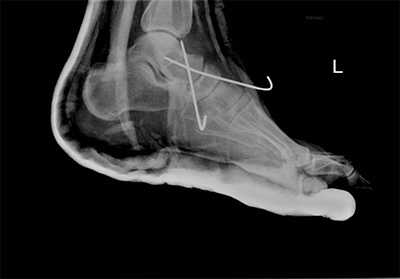

Пациент М. 1980 г.р., травму получил при падении на стопы с высоты 1,5 метра. Лечился по месту жительства (в травмпункте районной больницы) консервативно в гипсовой повязке в течение 14 дней. Консультирован в травматологическом отделении ФГБУ «УНИИТО им. В.Д. Чаклина» Минздрава РФ, предложено оперативное лечение. При поступлении кожные покровы стопы чистые, без признаков воспаления и сдавления тканей. Стопа отечна, уплощена. На рис. 1 представлены рентгенограммы пациента. Прооперирован через 2 недели после травмы. Операция состоит из двух этапов. Первый этап заключается в наложении дистракционного аппарата. Проводятся две спицы 1,8 мм во фронтальной плоскости: первая через нижнюю треть диафиза большеберцовой кости, вторая через бугор пяточной кости (рис. 2). Спицы фиксируются в дистракционном аппарате, выполненном из двух полуколец, соединенных между собой двумя телескопическими тягами. Особое расположение полуколец, фиксация спиц на концах полуколец, крепление кронштейнов для телескопических тяг обеспечивает тракцию пяточной кости в необходимом направлении с использованием минимального количества спиц и внешних опор при сохранении необходимого поля обзора для проведения рентгенологического и визуального контроля репозиции и фиксации. Второй этап - закрытая элевация импрессированной суставной поверхности и окончательная репозиция пяточной кости. Через разрез длиной до 1 см по латеральному краю ахиллова сухожилия (рис. 3) в месте его прикрепления к пяточной кости под соответствующий фрагмент подводится элеватор (рис. 4), манипуляцией которым устраняется смещение и выполняется провизорная фиксация спицами 1,5 мм (рис. 5). При сагиттальном раскалывании суставной фасетки целесообразно проведение одного-двух винтов субхондрально (рис. 6). Стержень вводится с дорзальной поверхности пяточной кости по ее оси через разрез до 2 см по предварительно сформированному остеотомом каналу (рис. 7, 8). Далее через проколы кожи с помощью кондуктора (рис. 9) выполняется запирание винтами с латеральной поверхности, внешнее устройство демонтируется. Достигнуто удовлетворительное стояние отломков (рис. 10).

Рис. 1. На рентгенограмме левой стопы в прямой и боковой проекциях определяется оскольчатый внутрисуставной перелом левой пяточной кости

Рис. 2. Первый этап оперативного лечения - наложение дистракционного аппарата